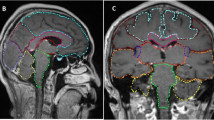

Pre-treatment gadolinium-enhanced T1-weighted magnetic resonance image (MRI) datasets of 865 patients with brain metastases from the years 2014–2018 were reviewed at the University of Luebeck, Germany. The HT-P area was contoured on axial planes for each patient as described previously by others [20, 21]. In short, minimal requirements for sufficient contouring and delineation were as following: CT images (axial planes) were fused to images obtained via T1-weighted MRI images (gadolinium contrast enhanced) acquired on 1.5 T resonance scans with a slice thickness of 1.5 mm. The hypothalamus and pituitary gland (including the pituitary stalk) were contoured on T1-weighted axial MRI sequences and a margin of 5 mm was added (see Fig. 1) [20, 21].

It is tempting to speculate that avoiding irradiation of the HT-P area by HT-P sparing WBI technique might lower endocrine and neurocognitive burden of classical WBI and preserve patients QoL. Recently, the groups of Fan and Marsh, respectively, showed that sparing of the hippocampus and the HT-P axis during WBI is technically feasible [20, 41]. However, the question remains whether the oncological prognosis is acceptable when sparing HT-P area during WBI. The reported low prevalence below 4% of HT-P involvement in our large cohort of patients with brain metastases argues for further studies to justify the concept of HT-P area sparing WBI in analogy to the hippocampus sparing technique recently introduced by Gondi and colleagues [19]. On the background of a low risk of 8.6% for hippocampal metastases in 371 patients with brain metastases [22], hippocampus sparing WBI has been established in many radiation oncology centers worldwide.